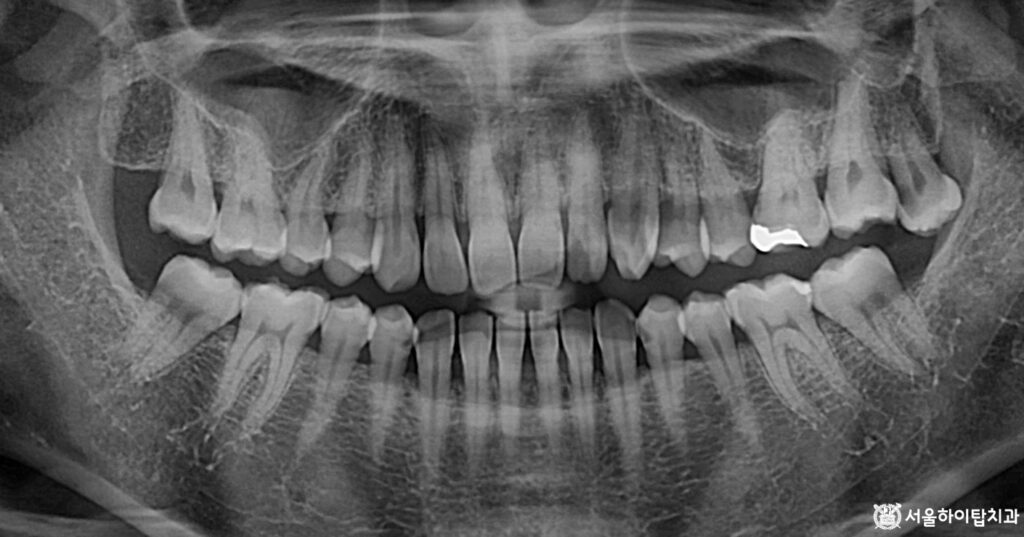

1. 초진

초진 파노라마 엑스레이입니다.

처음 보았을 때는 어디에 문제가 있는지

한눈에 파악하기 어렵습니다.

특히, 뿌리 부위의 파절이나 내부 염증은

엑스레이 상에서도 경계가 불분명하게

나타나는 경우가 많습니다.

즉, 엑스레이로도 판단이 쉽지 않다면,

실제 육안으로 더욱 어렵다고 할 수 있습니다.

따라서 이런 경우에는 Periapical radiograph,

즉 뿌리 끝까지 정밀하게 확인할 수 있는

국소 엑스레이를 추가로 촬영하여

진단하게 됩니다.

임상에서는 이를 ‘PA 촬영’

이라고 부르기도 합니다.